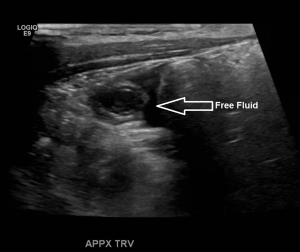

Appendix Ultrasound